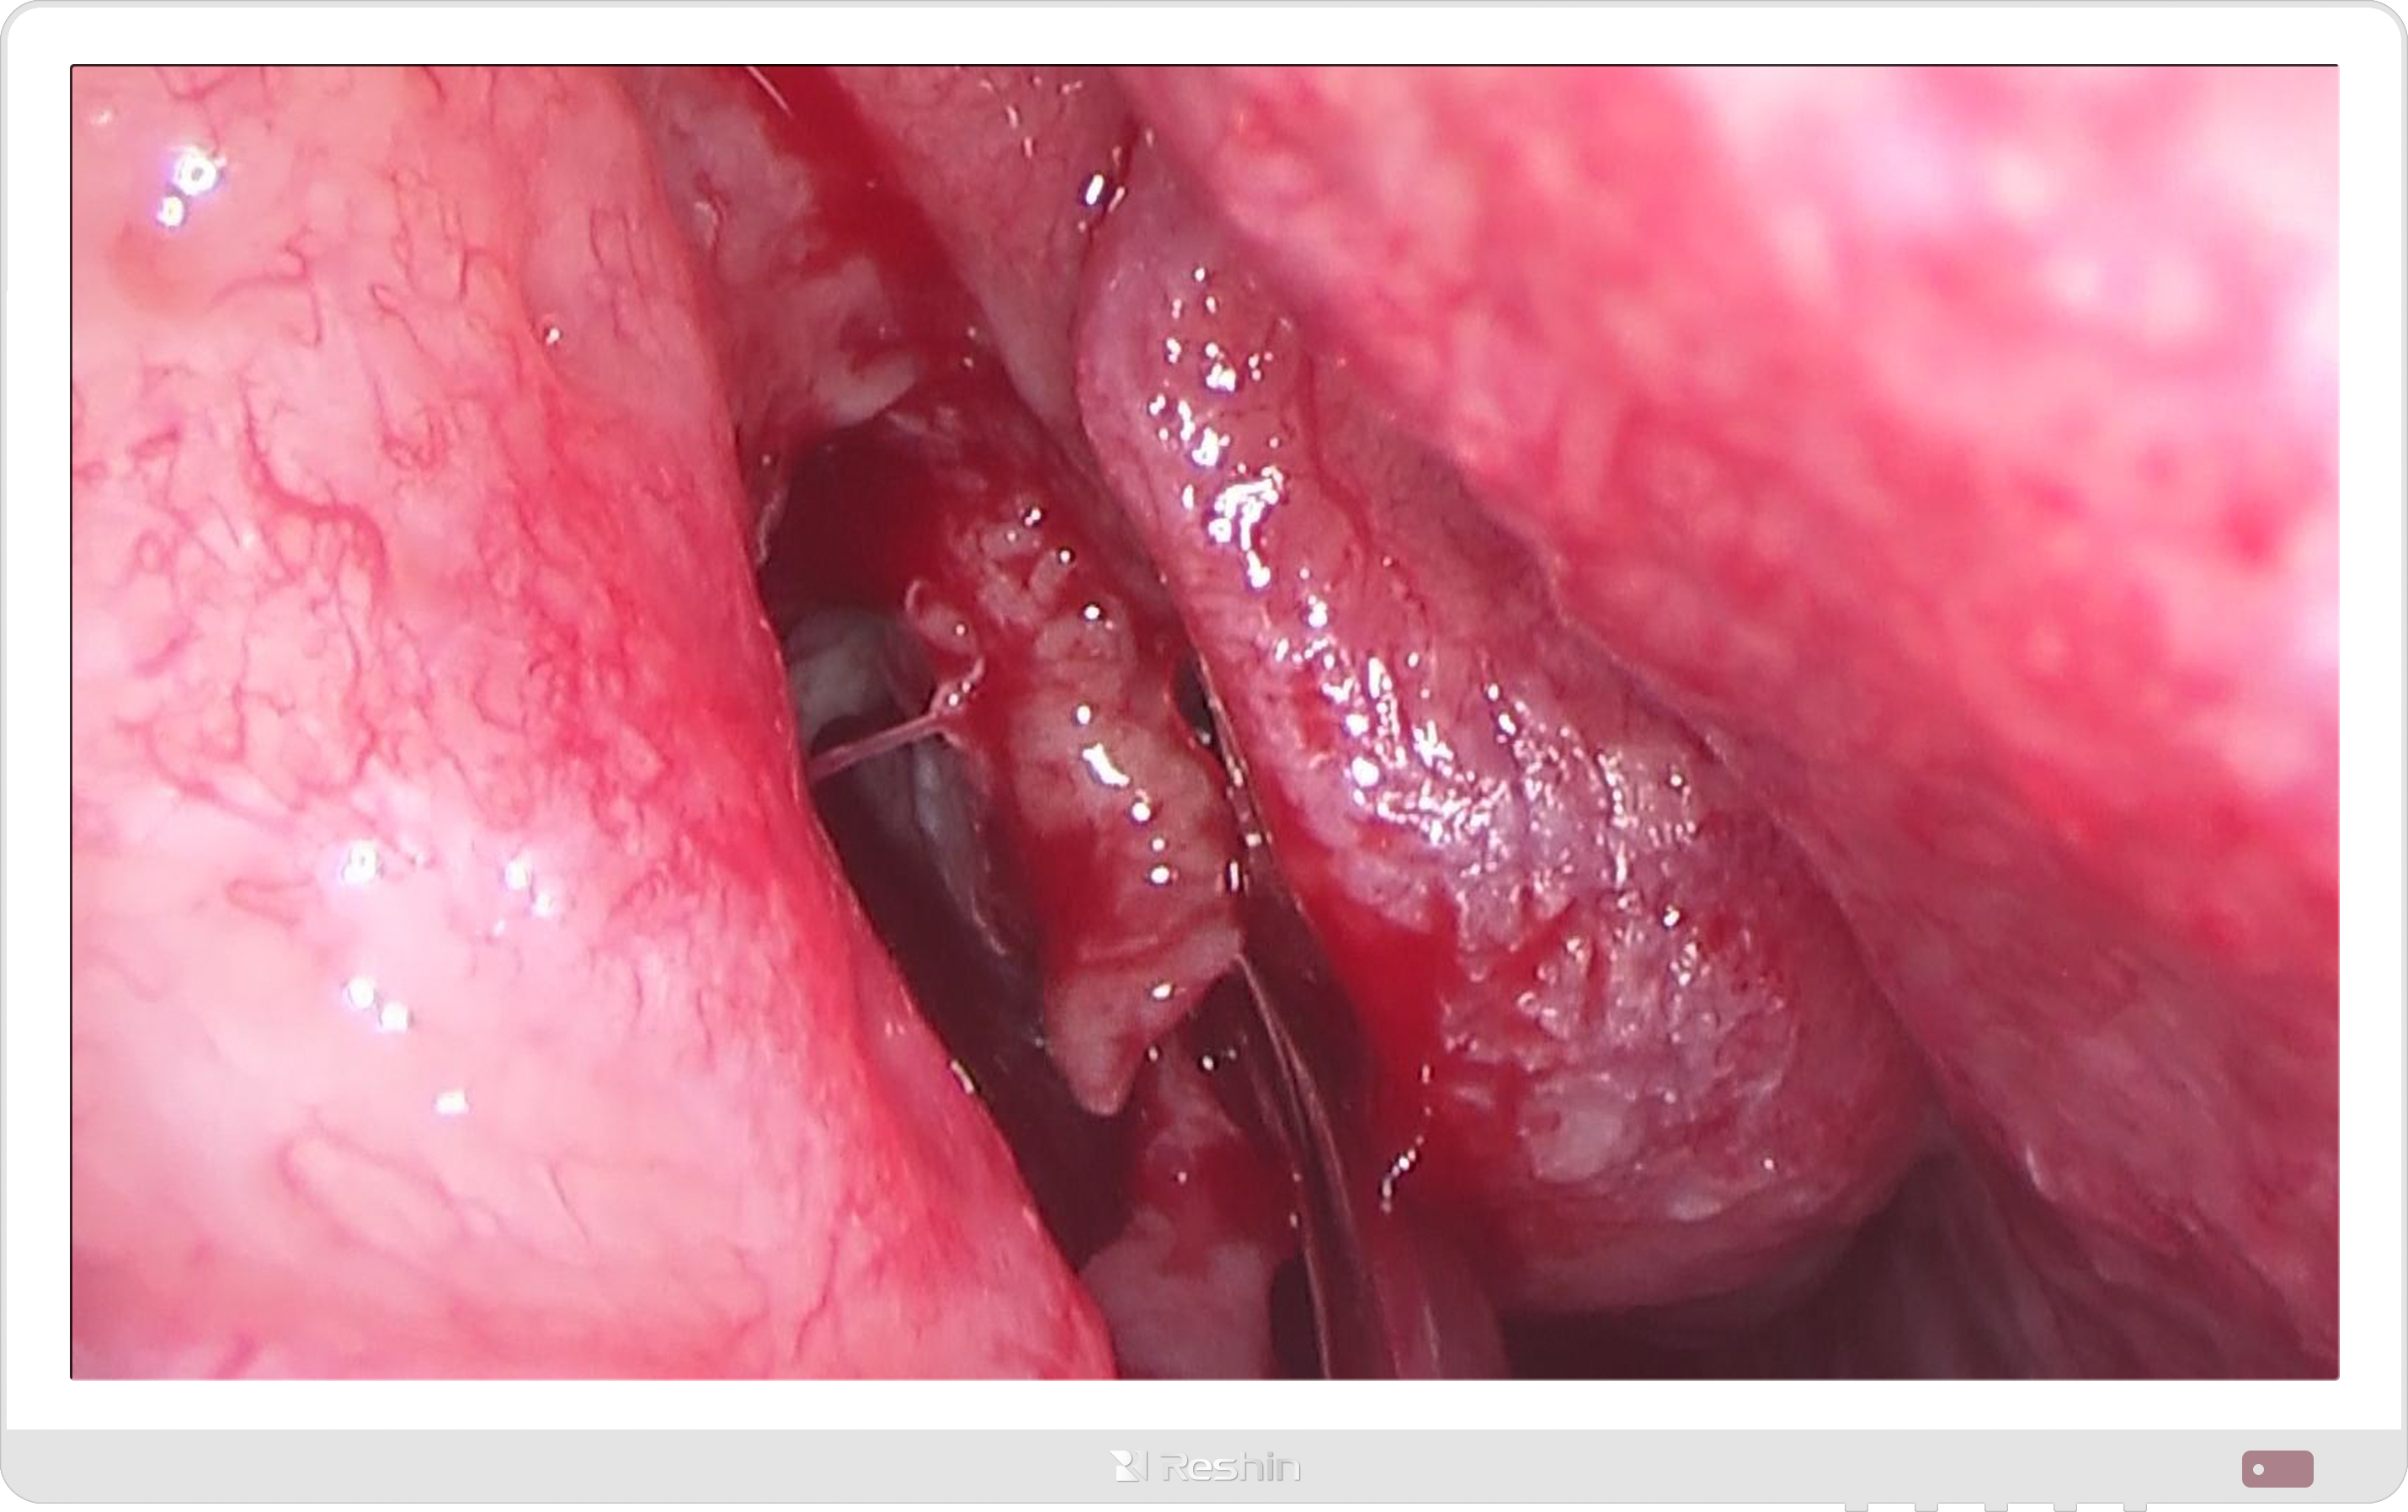

在应用场景上,外科手术显示器用途广泛。在腹腔镜、关节置换等手术中,它实时传输内镜影像,帮助医生避开关键器官;在影像诊断环节,为 CT、MRI 影像解读提供高清显示;在远程医疗领域,通过高清传输技术,让异地专家实时参与手术指导,打破空间限制。